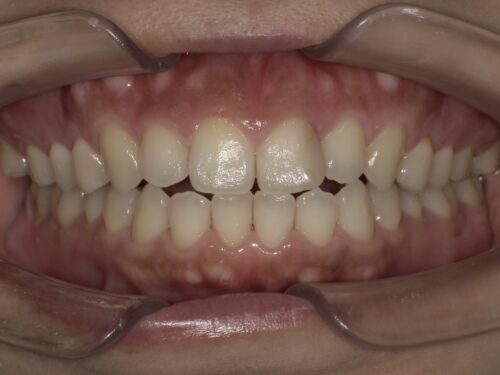

それぞれの段階で見比べてみましょう。

治療前

ホワイトニング後

コンポジットレジン後

詰め物を新しくした後は全体が白くなって、かつ、前歯のところも違和感がないですよね。